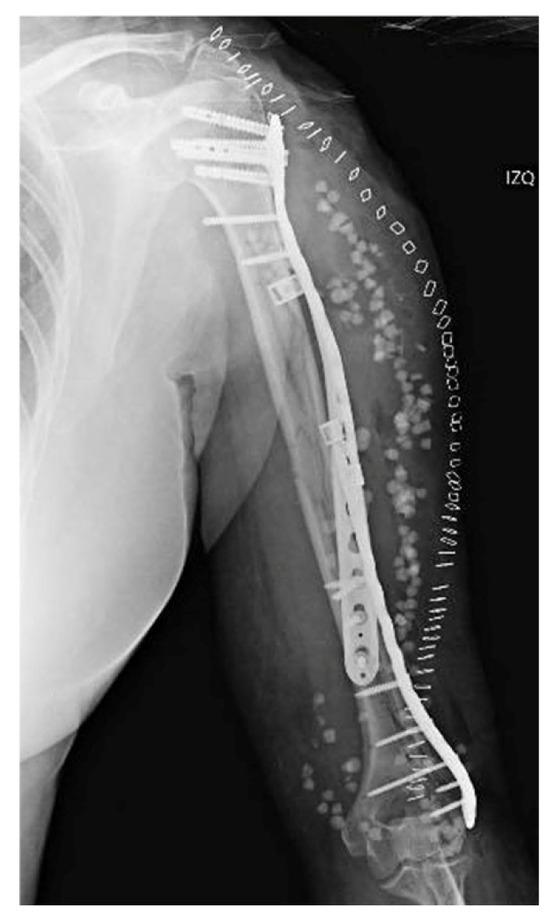

After reducing the fragments under fluoroscopic guidance, the two plates used to fix the fractures were supplemented by a locked extraarticular plate (LOQTEQ, aap Implantate AG, Berlin, Germany). Subsequently, and after a preliminary stabilization with K-wires, the fixation was reinforced by means of a long locked proximal humeral plate (Pantera, Toby Orthopaedics, Miami, FL, USA), which was helically contoured. The intermediate fragments were controlled using polymer cerclage bands (Ortholox, Ortolog Medical, Ankara, Turkey). Before closure, the stability of the fixation and the patient’s dynamic range of motion were checked and antibiotic-loaded calcium sulfate beads (Stimulan, Biocomposites, Staffordshire, UK) were applied as prophylaxis, as a local adjunct to systemic antibiotic therapy to enhance infection control in the context of a prolonged reoperation (Figure 4). Given the acute nature of the fracture, neither bone grafting nor postoperative electromagnetic therapy was deemed necessary. Initial immobilization was achieved by means of a Robert Jones bandage. Postoperative recovery proceeded uneventfully, with physical therapy being progressively introduced.

Two weeks after surgery, the patient achieved 100° flexion and −15° extension, without any kind of secondary displacements being radiographically apparent. At three months, X-rays demonstrated that healing was progressing satisfactorily, with the patient exhibiting a normal range of motion. The 6-month radiographs showed complete healing of the fracture, with the physical exam revealing a full range of motion. At one year from the procedure, function was assessed by means of the Disabilities of the Arm, Shoulder and Hand (DASH) scale and the Mayo Elbow Performance Score (MEPS), in which the patient obtained scores of 86 and 75 points, respectively (Figure 5). Simultaneously, the patient was referred to Rheumatology due to a low-energy fracture and a history suggestive of bone fragility. Osteoporosis was confirmed, and treatment with calcium, vitamin D, and antiresorptive therapy was initiated.

Figure 4. Postoperative anteroposterior view. Osteosynthesis with two precontoured helical plates and Stimulan antibiotic beads.

Figure 5. Radiographic follow-up at 6 months post-op.